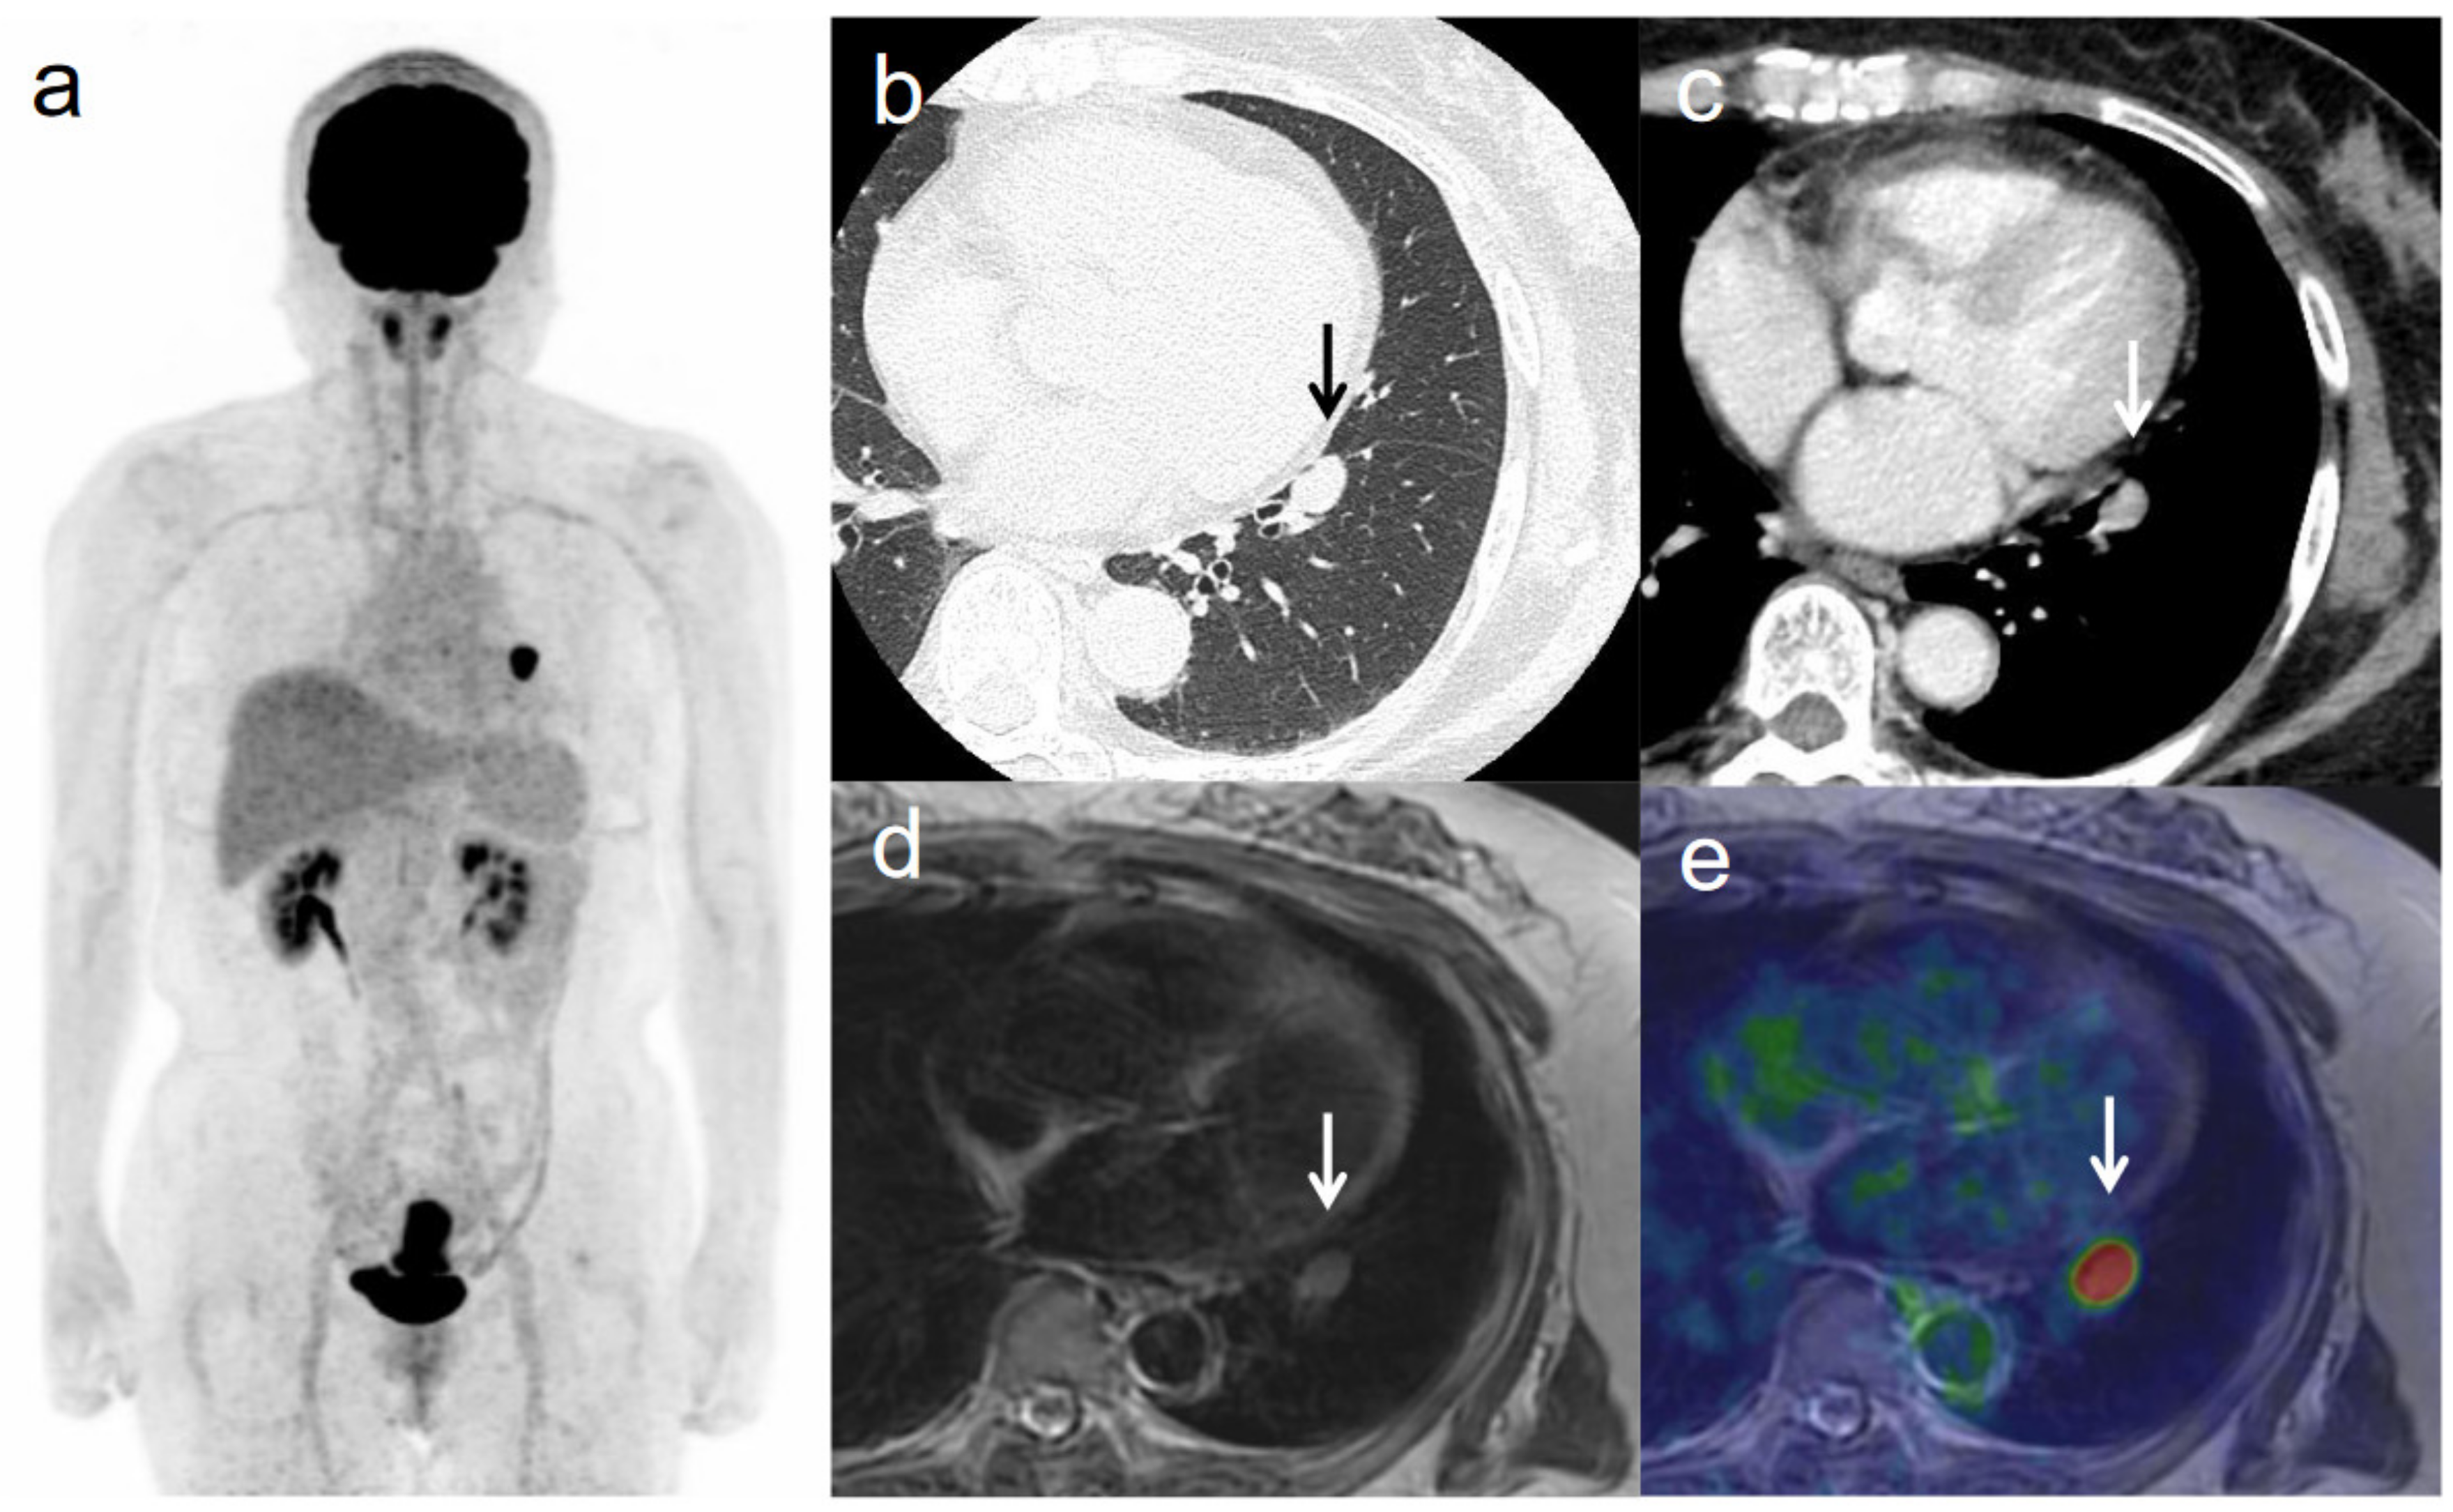

Figure 5. A 63-year-old woman with IVB cervical cancer and lung metastasis. (a) 18F-FDG PET image shows FDG uptake by tumor in the cervical cervix (arrow) and a lung nodule. (b) CT with lung window setting shows a lung nodule of short-axis diameter >1 cm (arrow). (c) CT of a lung nodule of short-axis diameter >1 cm (arrow). (d) Axial T2-weighted image shows a lung nodule of short-axis diameter >1 cm (arrow). (e) Axial T2-weighted PET/MR image shows FDG uptake by the lung nodule (arrow). This finding is strongly suggestive of lung metastasis, which was confirmed by histopathologic examination.

3.3. Revised FIGO Staging